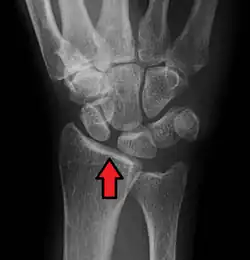

Dynamic scapholunate instability visible upon clenching the wrist -

X-ray images indicate scapholunate ligament instability when the scapholunate distance is more than 3 mm, which is called scapholunate dissociation.[7] A static scapholunate instability is generally readily visible, but a dynamic scapholunate instability can only be seen radiographically in certain wrist positions or under certain loading conditions, such as when clenching the wrist, or loading the wrist in ulnar deviation.[6]

In order to diagnose a SLAC wrist you need a posterior anterior (PA) view X-ray, a lateral view X-ray and a fist view X-ray.[8] The fist X-ray is often made if there is no convincing Terry Thomas sign. A fist X-ray of a scapholunate ligament rupture will show a descending capitate bone. Making a fist will give pressure at the capitate, which will descend if there is a rupture in the scapholunate ligament.